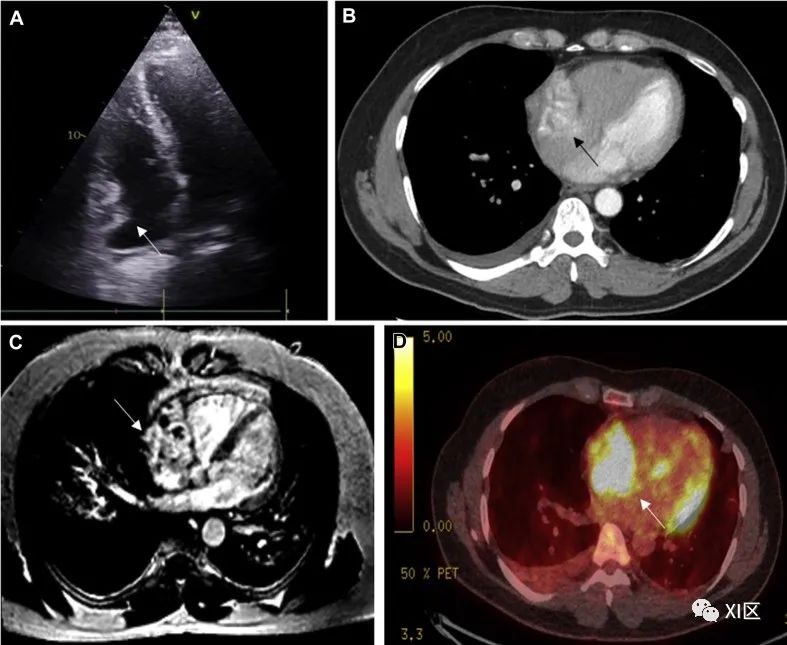

血管肉瘤(图 7)是一种侵袭性很强的肿瘤,由形状不规则的血管通道组成,内衬为无弹性上皮细胞,并伴有大面积坏死和出血。这种肿瘤好发于男性,发病高峰出现在人的第四个十年。约 75% 的病例源于右心房,通常充满心房,然后浸润到心包、三尖瓣、右心室和右冠状动脉。47% 至 89% 的患者会发生转移,最常见的是转移到肺部,但也会转移到骨骼、结肠和大脑。患者通常表现为右心衰竭症状、血心包引起的气短以及继发于室上性心律失常的心悸。

图 7 血管肉瘤58 岁男性,因咯血出现心脏血管肉瘤伴肺部转移。(A)超声心动图显示右心房有异型不规则肿块(白色箭头)。(B)肿块累及右心房(黑箭头),增强心脏 CT 显示肿块呈异质型,并伴有散在的非增强坏死区。右侧胸腔积液。(C)累及右心房的巨大肿块(白色箭头),跨越组织边界(浸润右心房并进入心包间隙和心外脂肪)。肿块血管丰富,CMR 晚期增强成像可见出血和坏死成分。(D)正电子发射计算机断层扫描(PET CT)显示右心房有不规则的高代谢活动区(白色箭头)。

在 TTE 上,血管肉瘤通常表现为右心房的回声结节状或分叶状肿块,伴有心包积液或直接心包扩展。心脏 CT 可评估肿瘤负荷和血管情况。肿瘤大体出血,由于散在的非强化坏死区,外观往往不均匀。确诊时,肿瘤侵犯邻近结构的情况很常见,很容易观察到心包积液和胸腔积液。当肿瘤侵入心包时,由于肿瘤细胞的分布和排列,心包通常会呈 "片状 "增厚,这与横纹肌肉瘤的结节状外观形成鲜明对比。在 CMR 的 T1 加权成像中,它们表现为等信号病变,伴有多个高强度结节区,通常被描述为 "菜花 "外观。肿瘤的晚期钆增强特征表现为异质性增强,可能会出现一个没有增强的大坏死核心。当肿瘤侵犯心包时,由于沿肿瘤突出的血管呈钆强化,通常被描述为 "太阳射线 "外观。